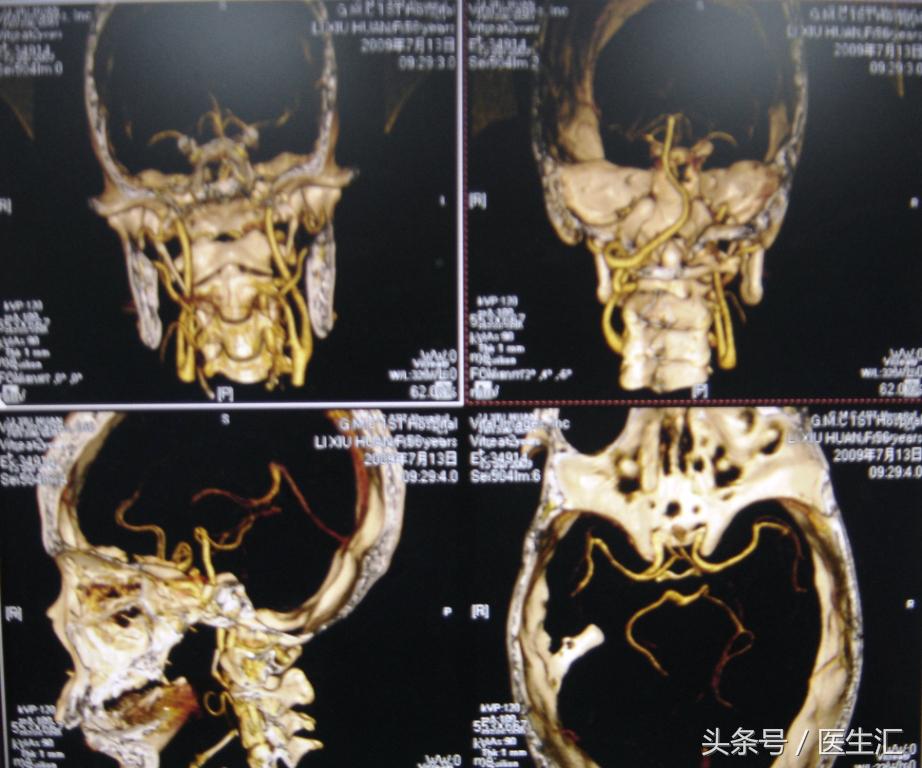

2、头颅MRI、MRA及脑血管三维重建(图12、13、14)